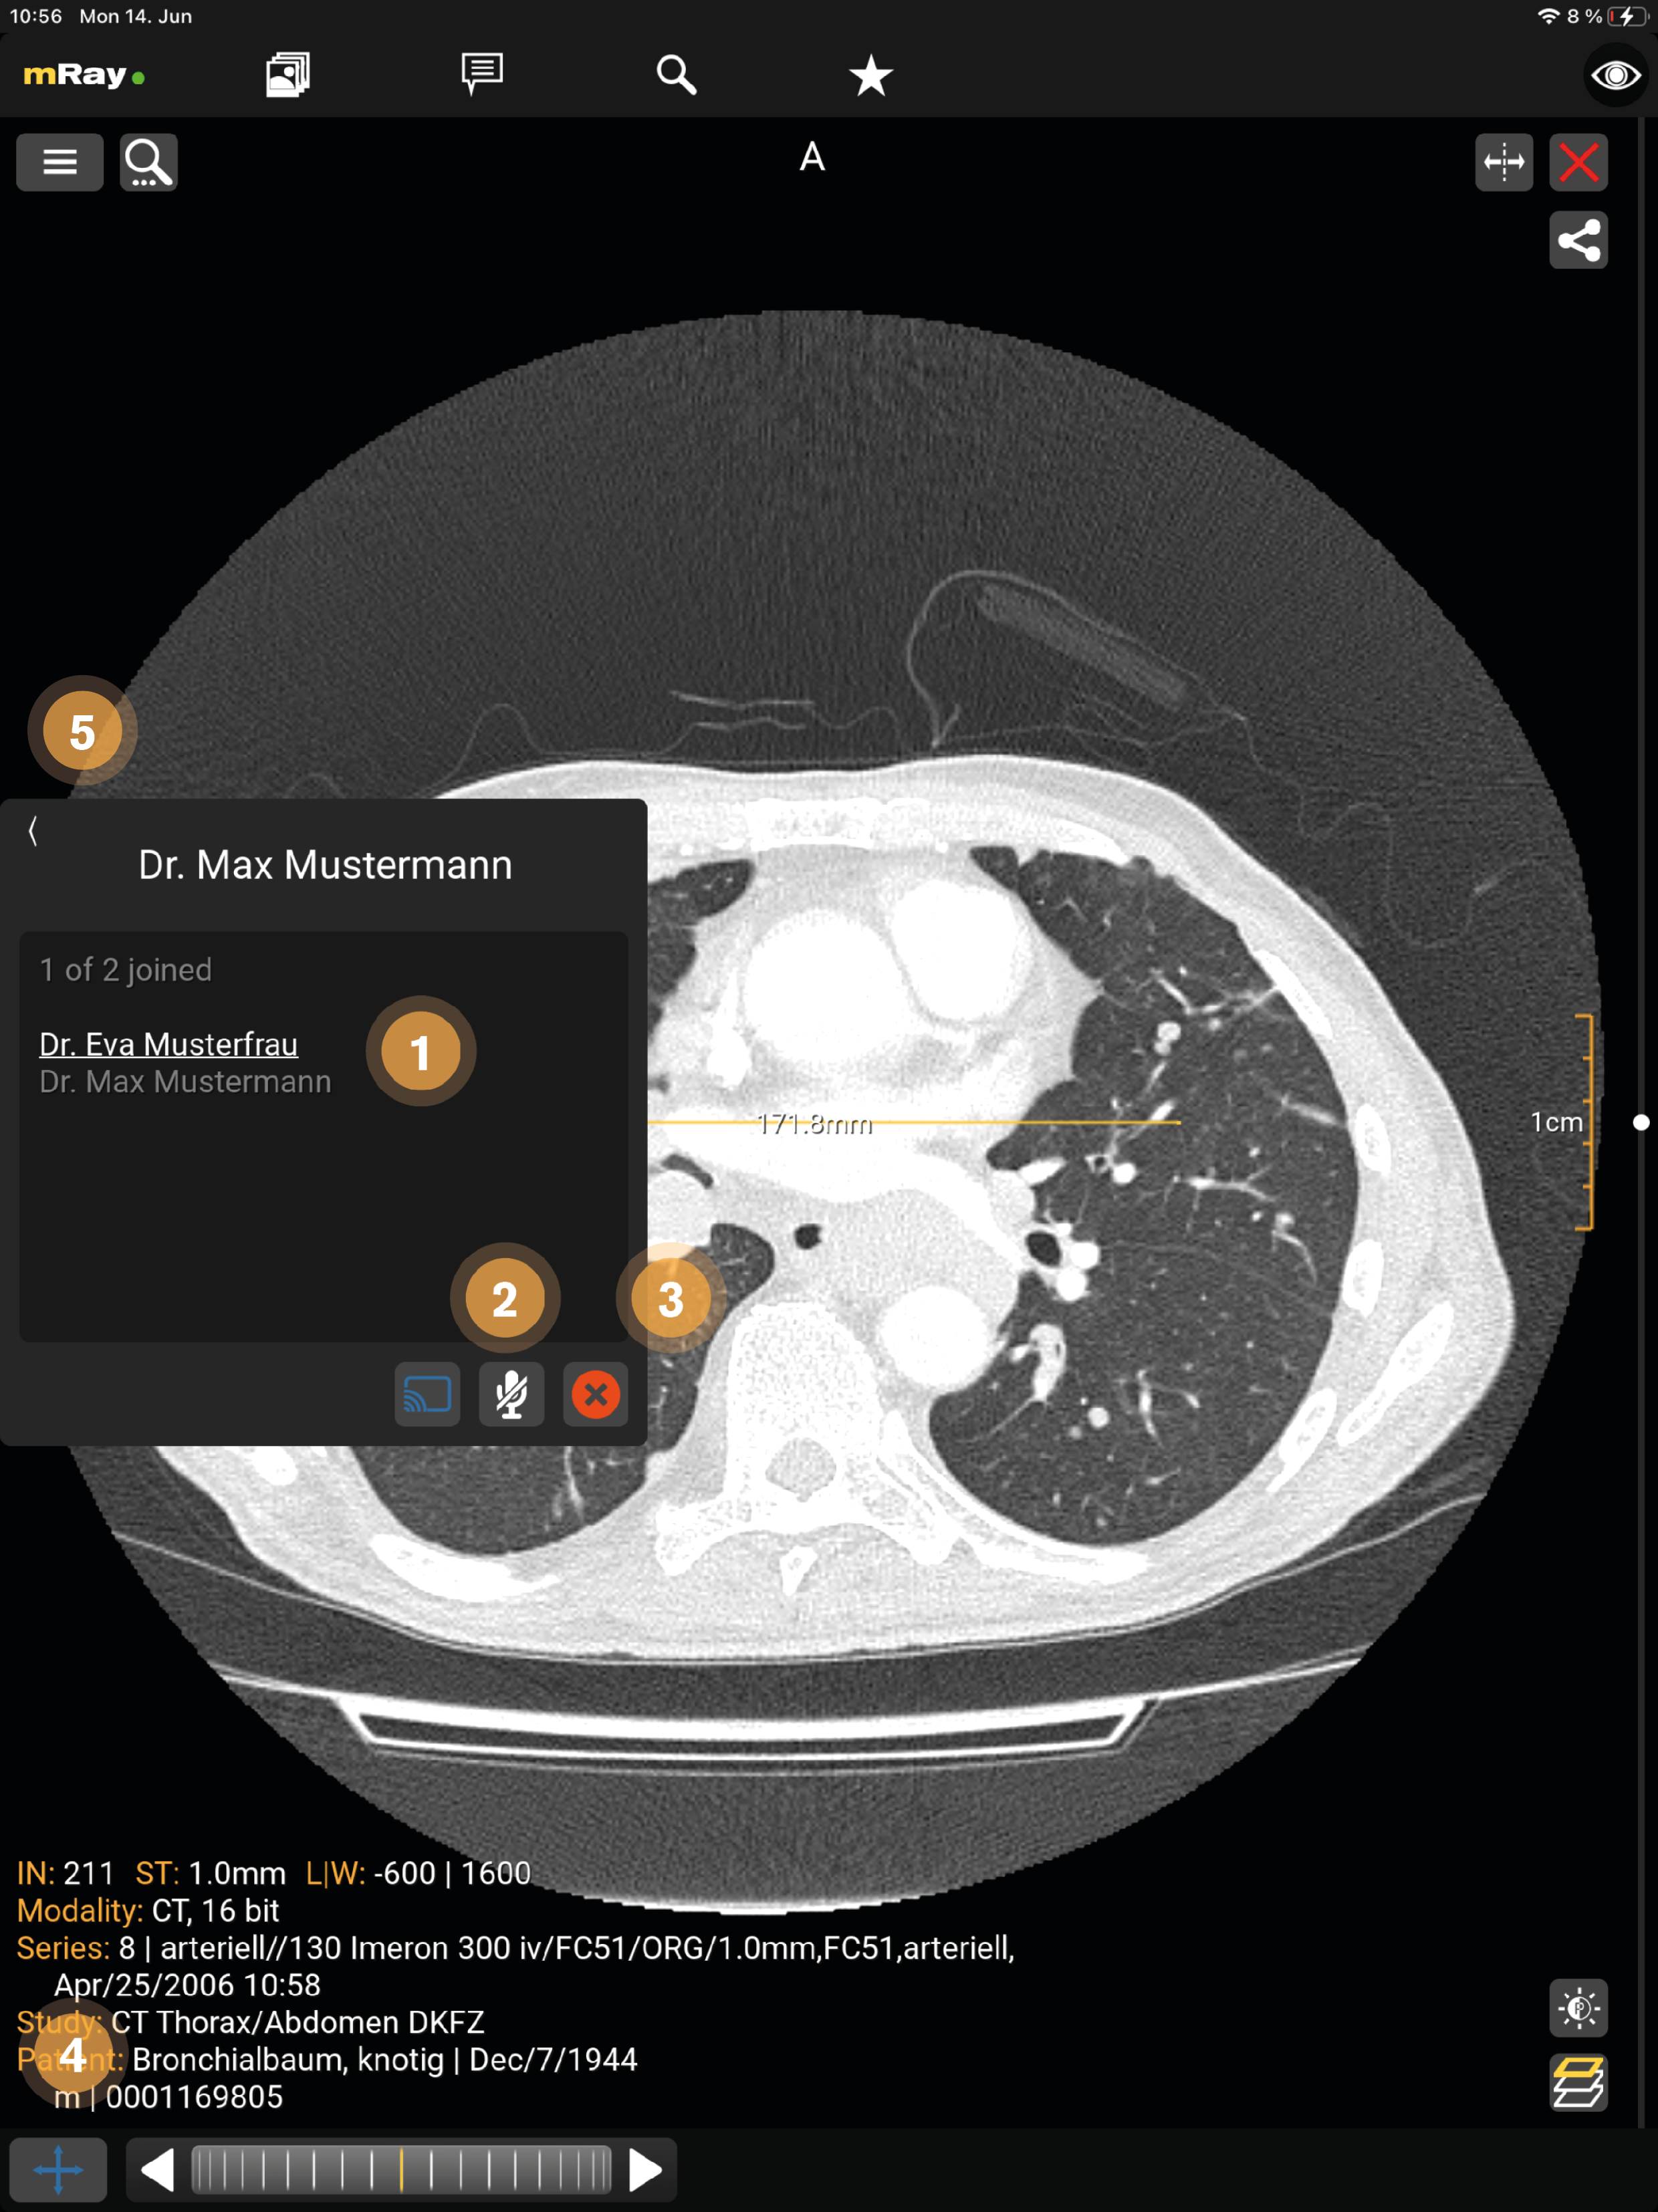

14. Screensharing

Das Screensharing ermöglicht es, Ihren Bildschirm mit anderen zu teilen. Nach der Betätigung des Buttons (siehe Chat) startet das Screensharing und es öffnet sich das bereits von Ihnen geöffnete Bild (siehe Chat) oder Sie werden an die Inbox weitergeleitet, wenn noch kein Bild geöffnet wurde. Das Screensharing kann mit einer oder mehreren Personen (siehe Screensharing in Gruppen), in Form einer Gruppe, gestartet werden.

In einem Chat ist derjenige Administrator, der das Screensharing startet. In einer Gruppe wird der Administrator zuvor festgelegt (siehe Screensharing in Gruppen).

Die Ansicht stellt folgende Funktionen zur Verfügung:

-

Derjenige der das Screensharing gestartet hat wird weiß unterstrichen, die aktiven Teilnehmer werden weiß und die inaktiven Teilnehmer der Gruppe grau dargestellt.

-

Mit dem "Mikrofon"-Button kann ein Teilnehmer die Sprachfunktion aktivieren und beenden (durchgestrichen). Der sprechende Teilnehmer wird gelb dargestellt.

-

Durch den X-Button kann das Screensharing verlassen werden.

-

Nur der Administrator kann während des Screensharings Werkzeuge anwenden.

-

Hier kann das Fenster minimiert werden.